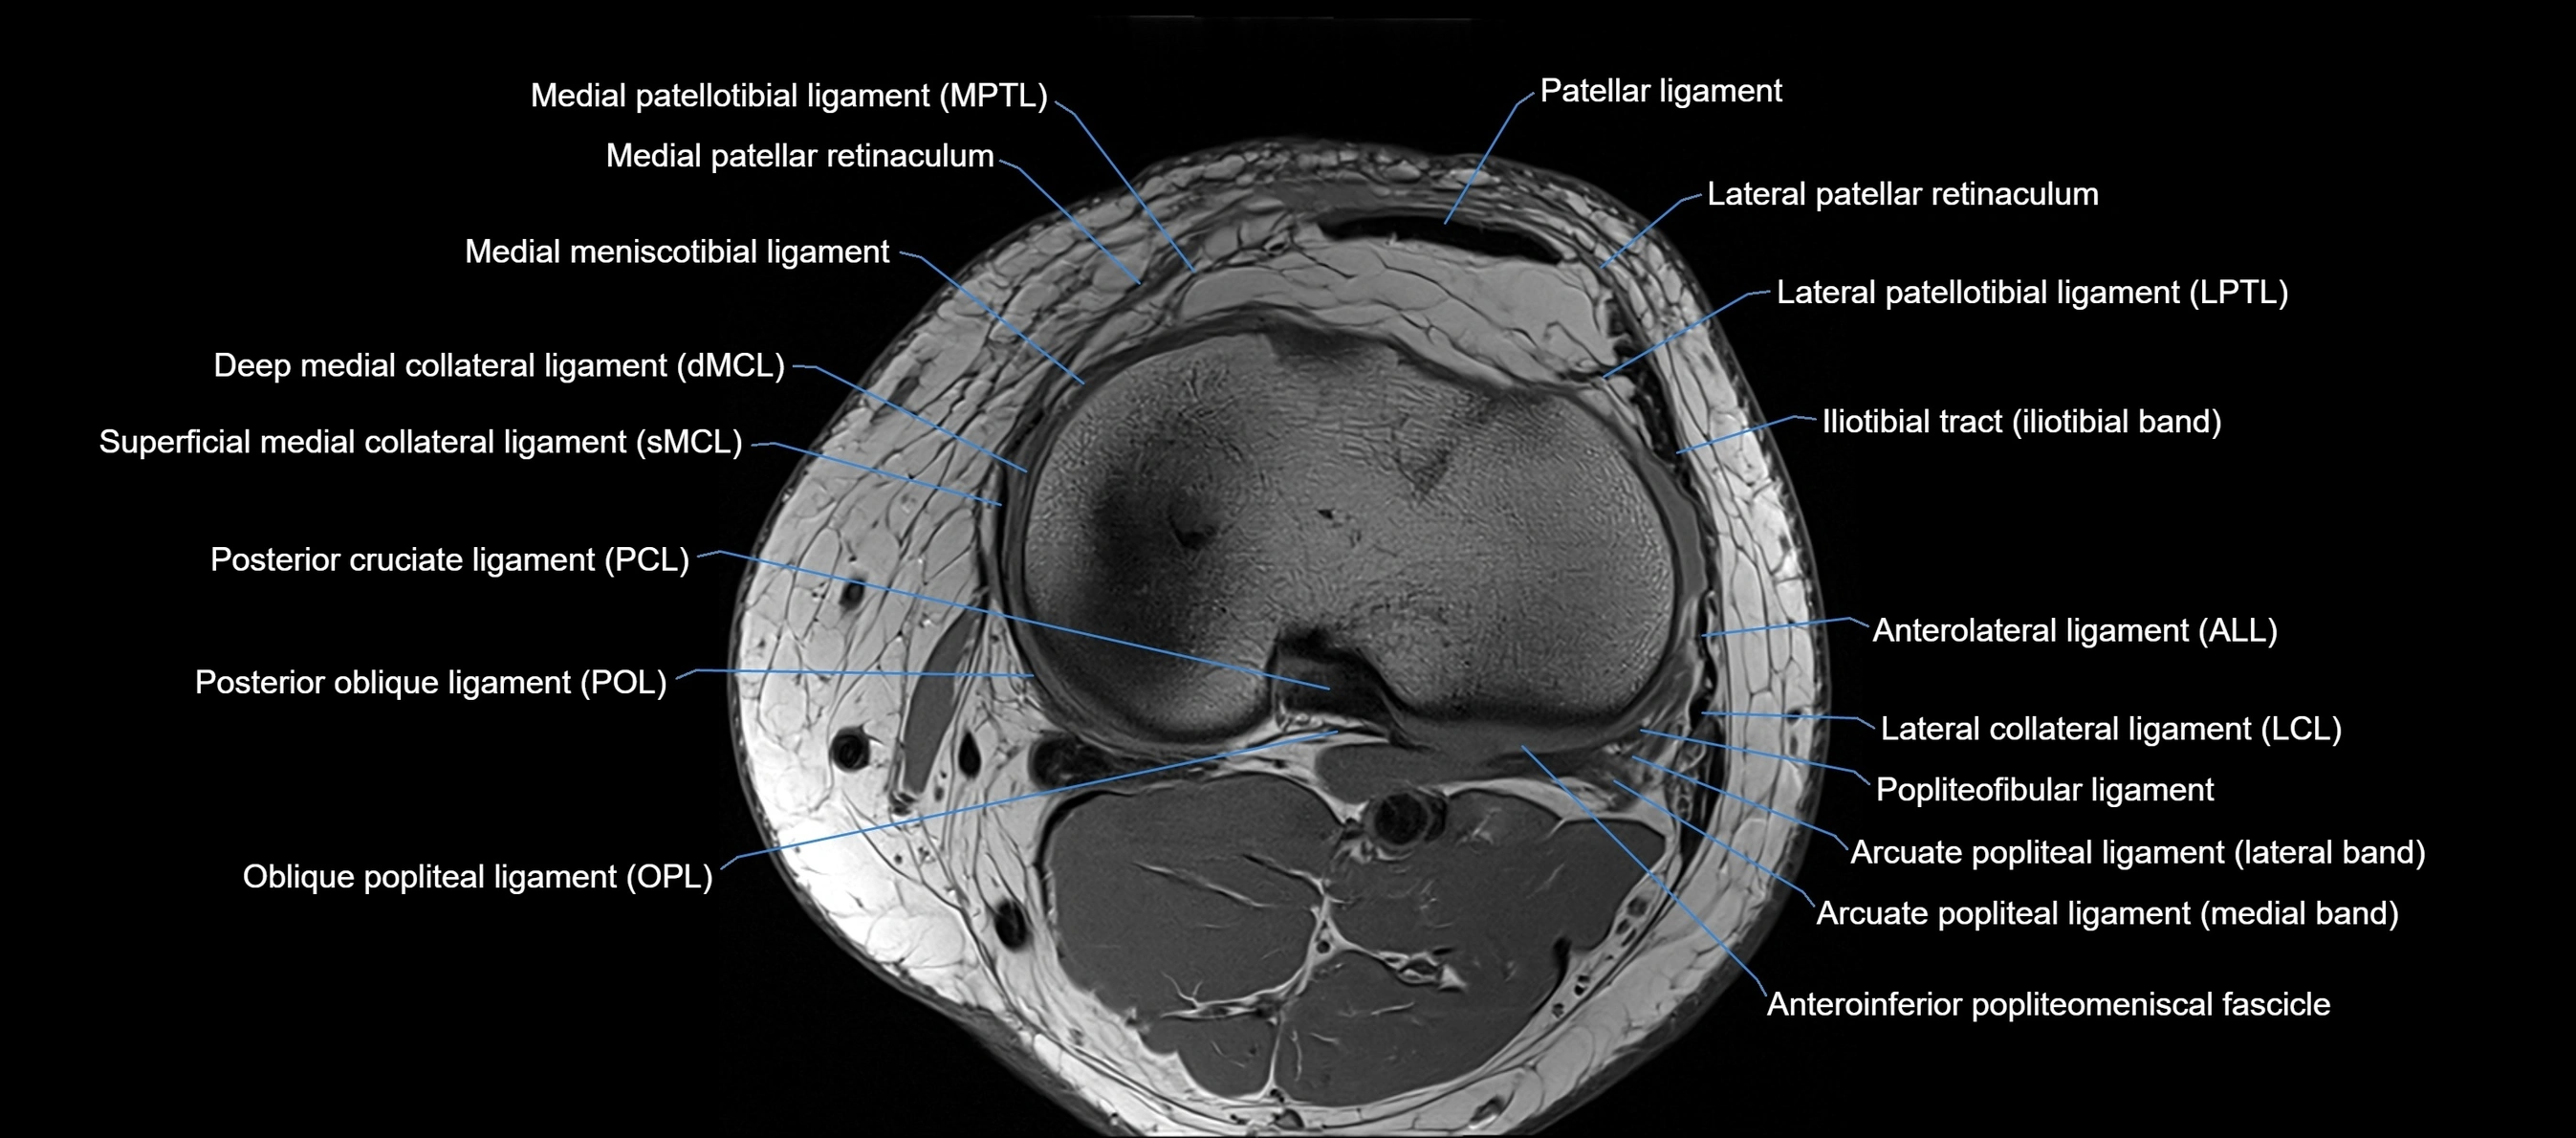

MRI Appearance

T1-weighted images:

• Normal ACL appears as a low-signal band-like structure crossing the intercondylar notch

• Surrounded by intermediate signal synovial fluid and fat planes

T2-weighted images:

• Normal ACL remains low signal

• Partial or complete tears appear as discontinuity, increased signal, or fiber laxity

MRI images

image